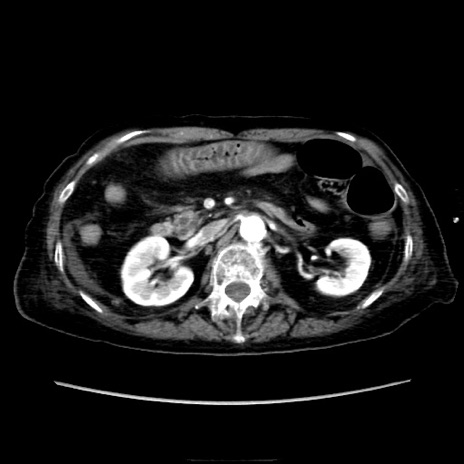

症例40(横断像)

横断像